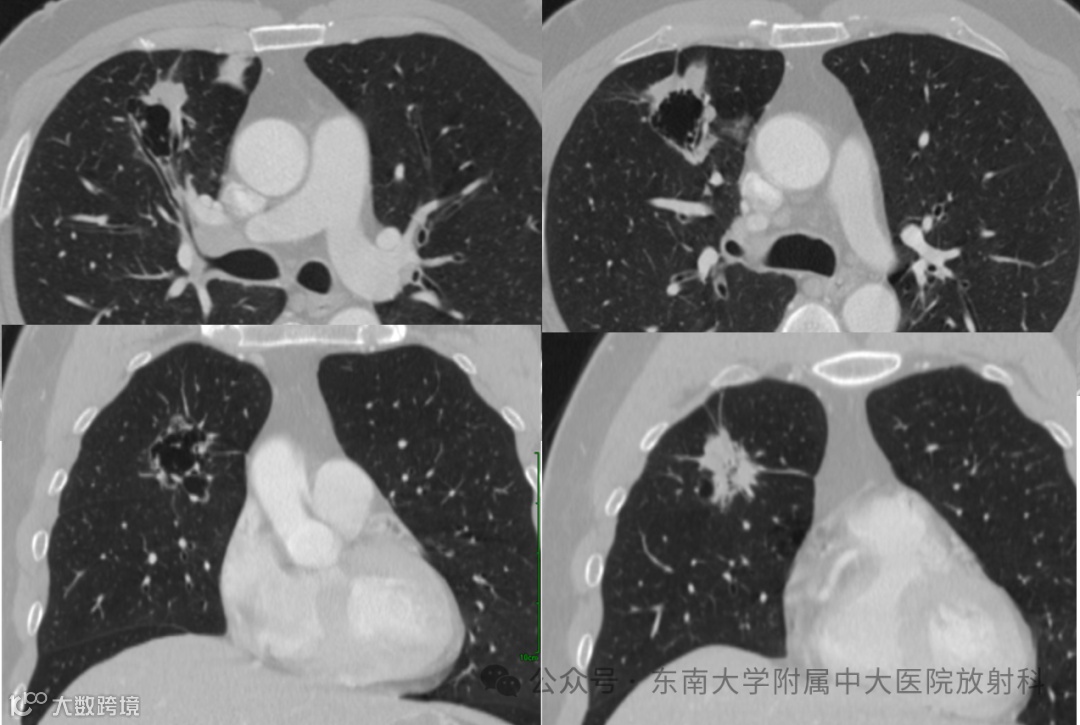

现病史:患者 6 天前体检时查胸部CT 示:右肺上叶不规则空腔样病变,占位待排,建议结合临床病史及增强检查,必要时穿刺活检。患者偶有咳嗽、气喘,无咳痰,晚夜间睡眠时有打鼾,无恶心呕吐。今为求进一步诊治,至我院门诊,拟“右上肺占位”收住院。一般情况良好 -

影像学检查: 胸部、腹盆部增强CT(1683572XXF)

影像学表现